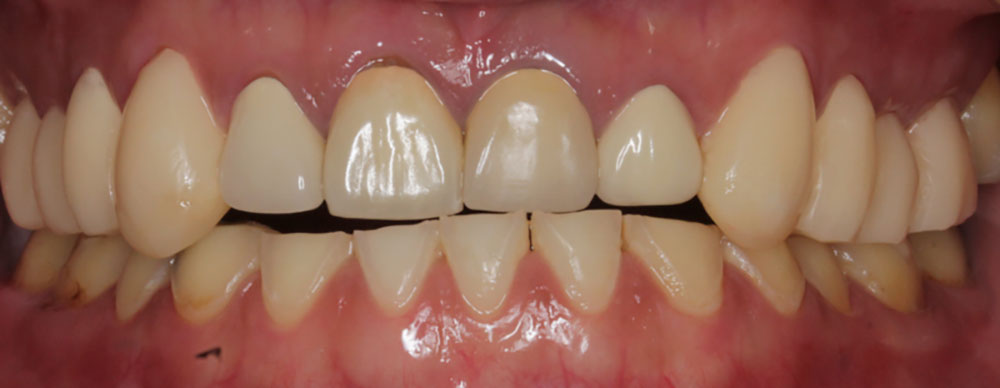

3-2.歯がすり減る

歯がすり減る

歯が擦り合わされることによって、歯がどんどん削られてしまい、短くなってしまいます。

それにより、歯の噛み合わせがうまくいかなくなり、また歯きしりがするという悪循環となってしまいます。